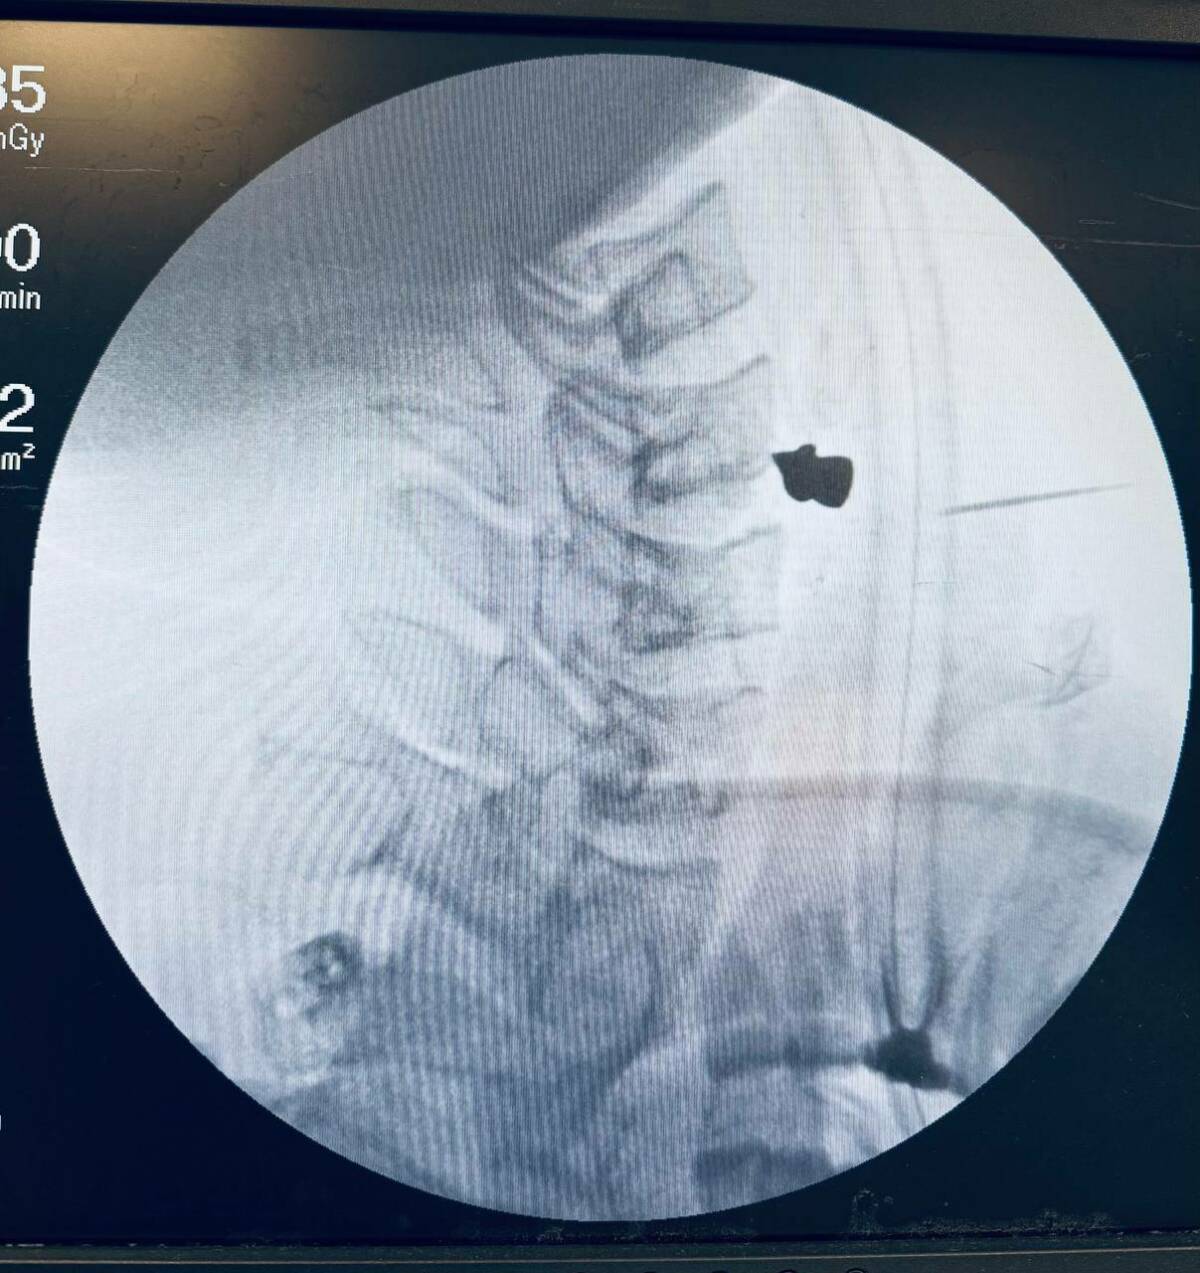

Пуля прошла через шею и остановилась в позвоночнике. Чудом она не задела ни одну артерию, трахею или пищевод. Пациент чувствовал боль, ему было трудно глотать и говорить.

Заведующий ЛОР-отделением Марат Гилялов и заведующий отделением нейрохирургии №2 Георгий Майков провели ювелирную операцию. Им удалось аккуратно извлечь пулю и зашить рану всего за 20 минут.